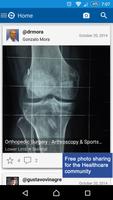

全球医疗保健专业人员的图像共享网络

InsightMedi是医疗保健专业人员的免费图像共享平台。在为您创建的社区中,上传,共享和与全球医疗保健专业人员创建的内容上的内容。

通过与同事建立联系并通过咨询,协作和讨论建立新联系,从而参与全球医疗保健专业人员网络。 InsightMedi提供了安全,安全共享,扩展和完善您的医疗专业知识的工具。每次打开应用程序时,都可以利用从世界各地发现真实的临床案例图像和视频的能力。